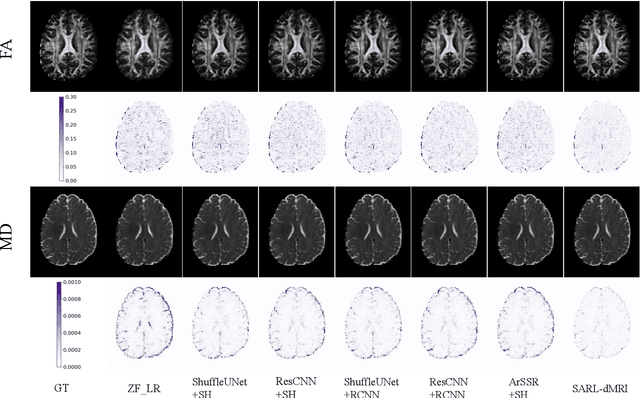

Abstract:Diffusion magnetic resonance imaging (dMRI) often suffers from low spatial and angular resolution due to inherent limitations in imaging hardware and system noise, adversely affecting the accurate estimation of microstructural parameters with fine anatomical details. Deep learning-based super-resolution techniques have shown promise in enhancing dMRI resolution without increasing acquisition time. However, most existing methods are confined to either spatial or angular super-resolution, limiting their effectiveness in capturing detailed microstructural features. Furthermore, traditional pixel-wise loss functions struggle to recover intricate image details essential for high-resolution reconstruction. To address these challenges, we propose SARL-dMRI, a novel Spatial-Angular Representation Learning framework for high-fidelity, continuous super-resolution in dMRI. SARL-dMRI explores implicit neural representations and spherical harmonics to model continuous spatial and angular representations, simultaneously enhancing both spatial and angular resolution while improving microstructural parameter estimation accuracy. To further preserve image fidelity, a data-fidelity module and wavelet-based frequency loss are introduced, ensuring the super-resolved images remain consistent with the original input and retain fine details. Extensive experiments demonstrate that, compared to five other state-of-the-art methods, our method significantly enhances dMRI data resolution, improves the accuracy of microstructural parameter estimation, and provides better generalization capabilities. It maintains stable performance even under a 45$\times$ downsampling factor.